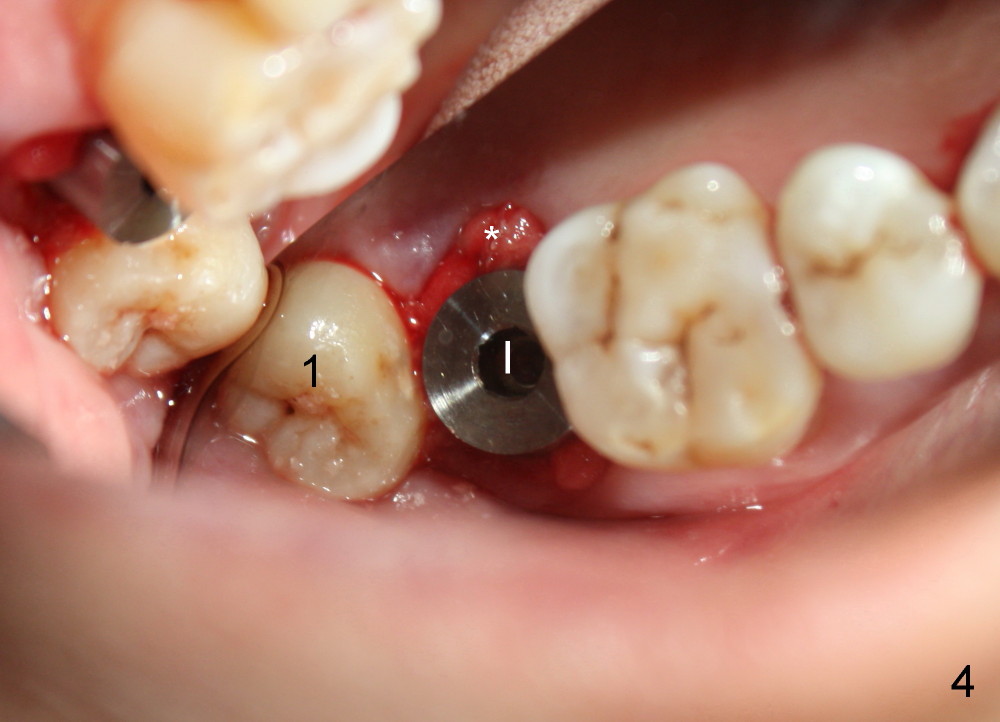

A 48-year-old lady is a dental phobic and has generalized chronic periodontitis. Bone loss around the tooth #2 has been severe for the last 5 years (Fig.1,2 *). Finally she agrees to have #2 (symptomatic) extracted and immediate implant placed (Fig.3 I). A 7x17 mm implant has to be used to achieve primary stability. The remaining buccal and lingual gaps are filled with allograft and membrane (Fig.4 *). Fig.5 shows that there is a space between the tooth #1 (asymptomatic) and the immediate implant (I). The wound/socket is protected by applying perio dressing around an abutment (Fig.6 A). Postop the patient is pain free; the perio dressing dislodges by itself. She returns 3.5 months later for restoration; but the tooth #1 has shifted mesially (Fig.6 arrow). The patient is not so willing to have #1 removed. Bands and bracket are placed in the neighboring teeth including a provisional crown to move the shifted tooth (with mobility) distally (Fig.7,9). The 2nd reason for #1 shifting is abnormal occlsual scheme on the right posterior region (Fig.8); mobility of #1 is the 1st one. The 3rd one is probably bruxism. In 5-6 weeks, the tooth #1 has moved to a desirable position (Fig.10, as compared to Fig.3,5). There is enough space for restoration (Fig.11,12).